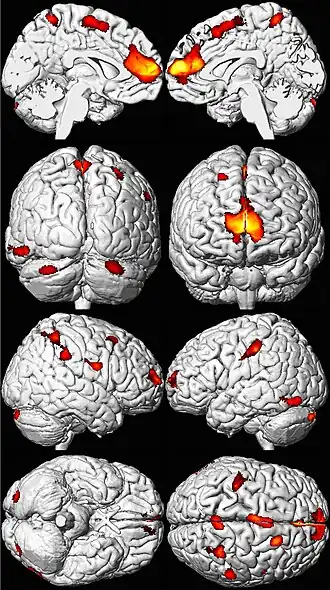

Les zones de perte de volume cérébral apparaissent ici en couleur sur un modèle de cerveau normal[201].

L'exposition de l'embryon ou de l'enfant, jusqu'à l'adolescence peut avoir des effets différés délétères et graves, parfois irréversibles, qui commencent à préoccuper le politique, les responsables de la santé, les assureurs et certains économistes.

Le plomb moléculaire n'est en effet ni biodégradable, ni dégradable. Et, étant bioaccumulable, il restera pour cette raison longtemps un problème de santé publique dans la plupart des pays, en dépit de son interdiction d'usage dans l'essence et les peintures et certaines cartouches de chasse.